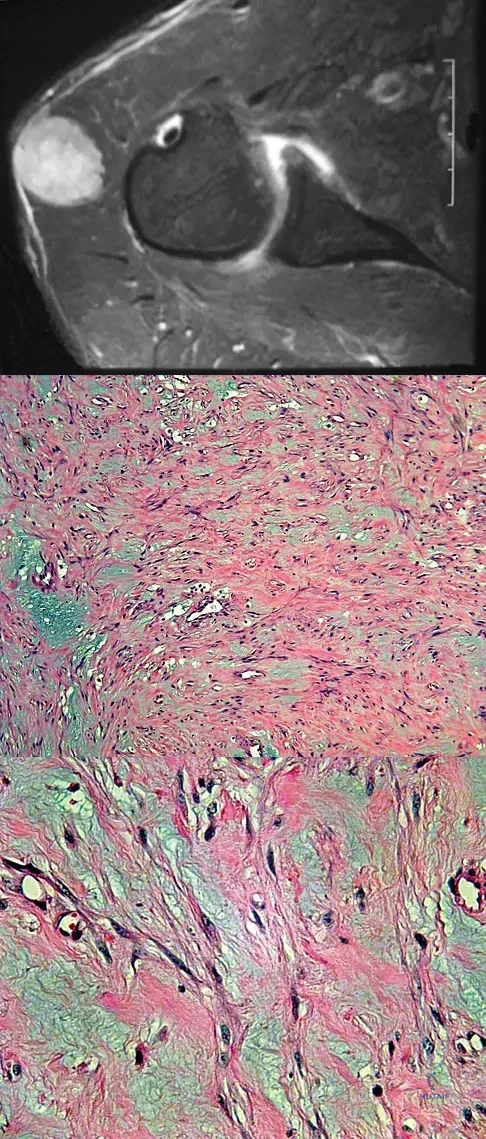

A 13-year-old boy has knee pain after sustaining a mild twisting injury while playing basketball 4 weeks ago. Radiographs and MRI scans are shown in Figures 24a through 24d, and biopsy specimens are shown in Figures 24e and 24f. Treatment should consist of